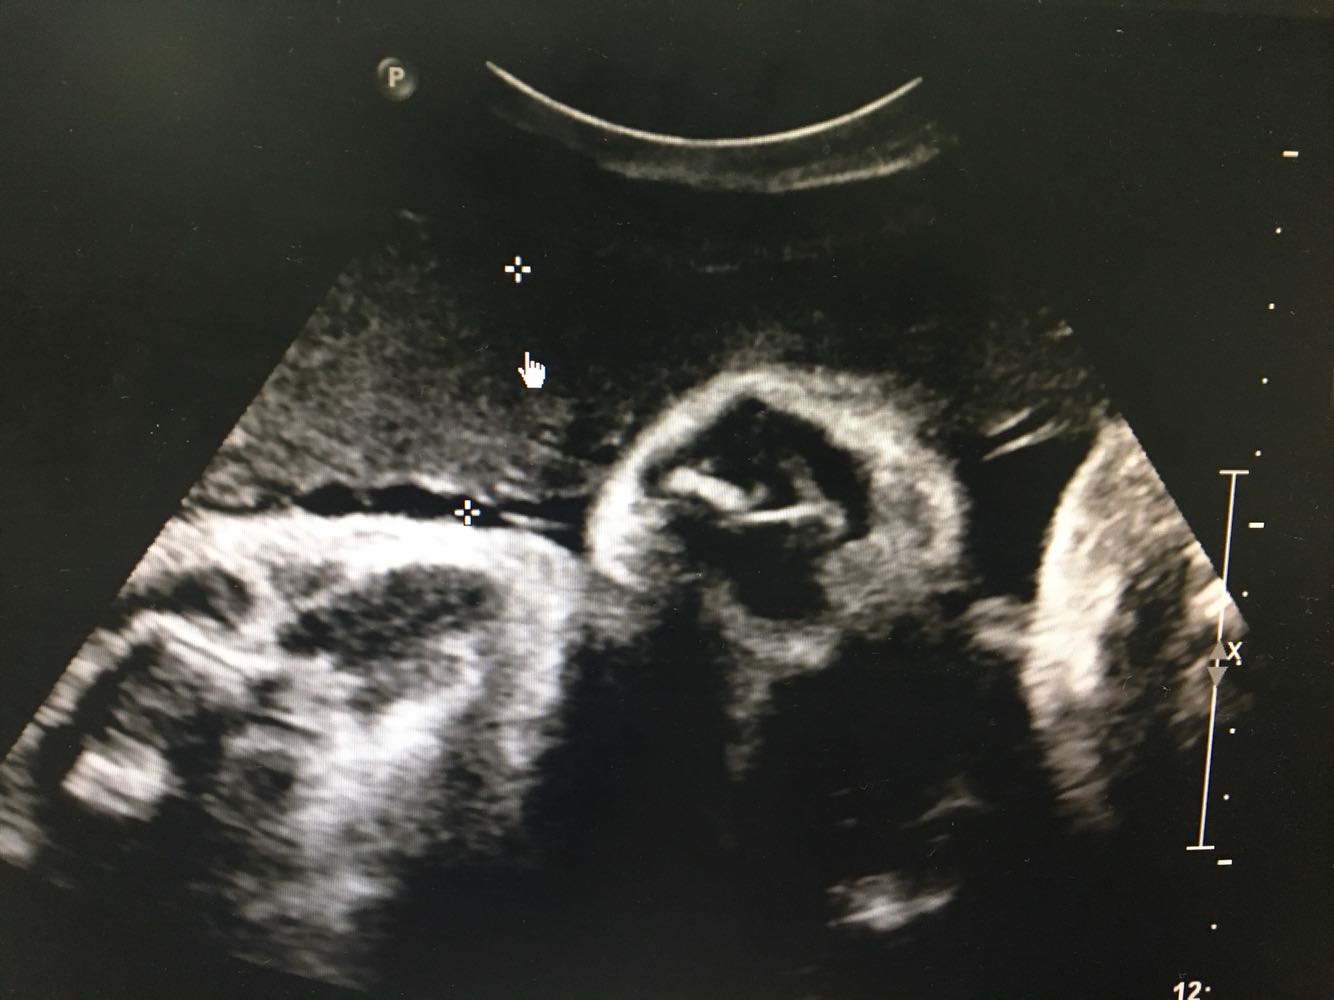

B超:胎头位于:耻上; 双顶径: 95 mm; 头围长: 339 mm; 腹围长: 327 mm; 股骨长: 75 mm; 肱骨长: 59 mm; 胎动胎心:佳(胎心率:143次/分); 胎盘附着于:宫体,前壁;分期:II期;胎盘厚度: 32 mm。 羊水指数: 43 、23 、51 、49 mm。 胎儿颈部未见脐血流信号。脐动脉血流 S/D 2.8 ,RI 0.65 。